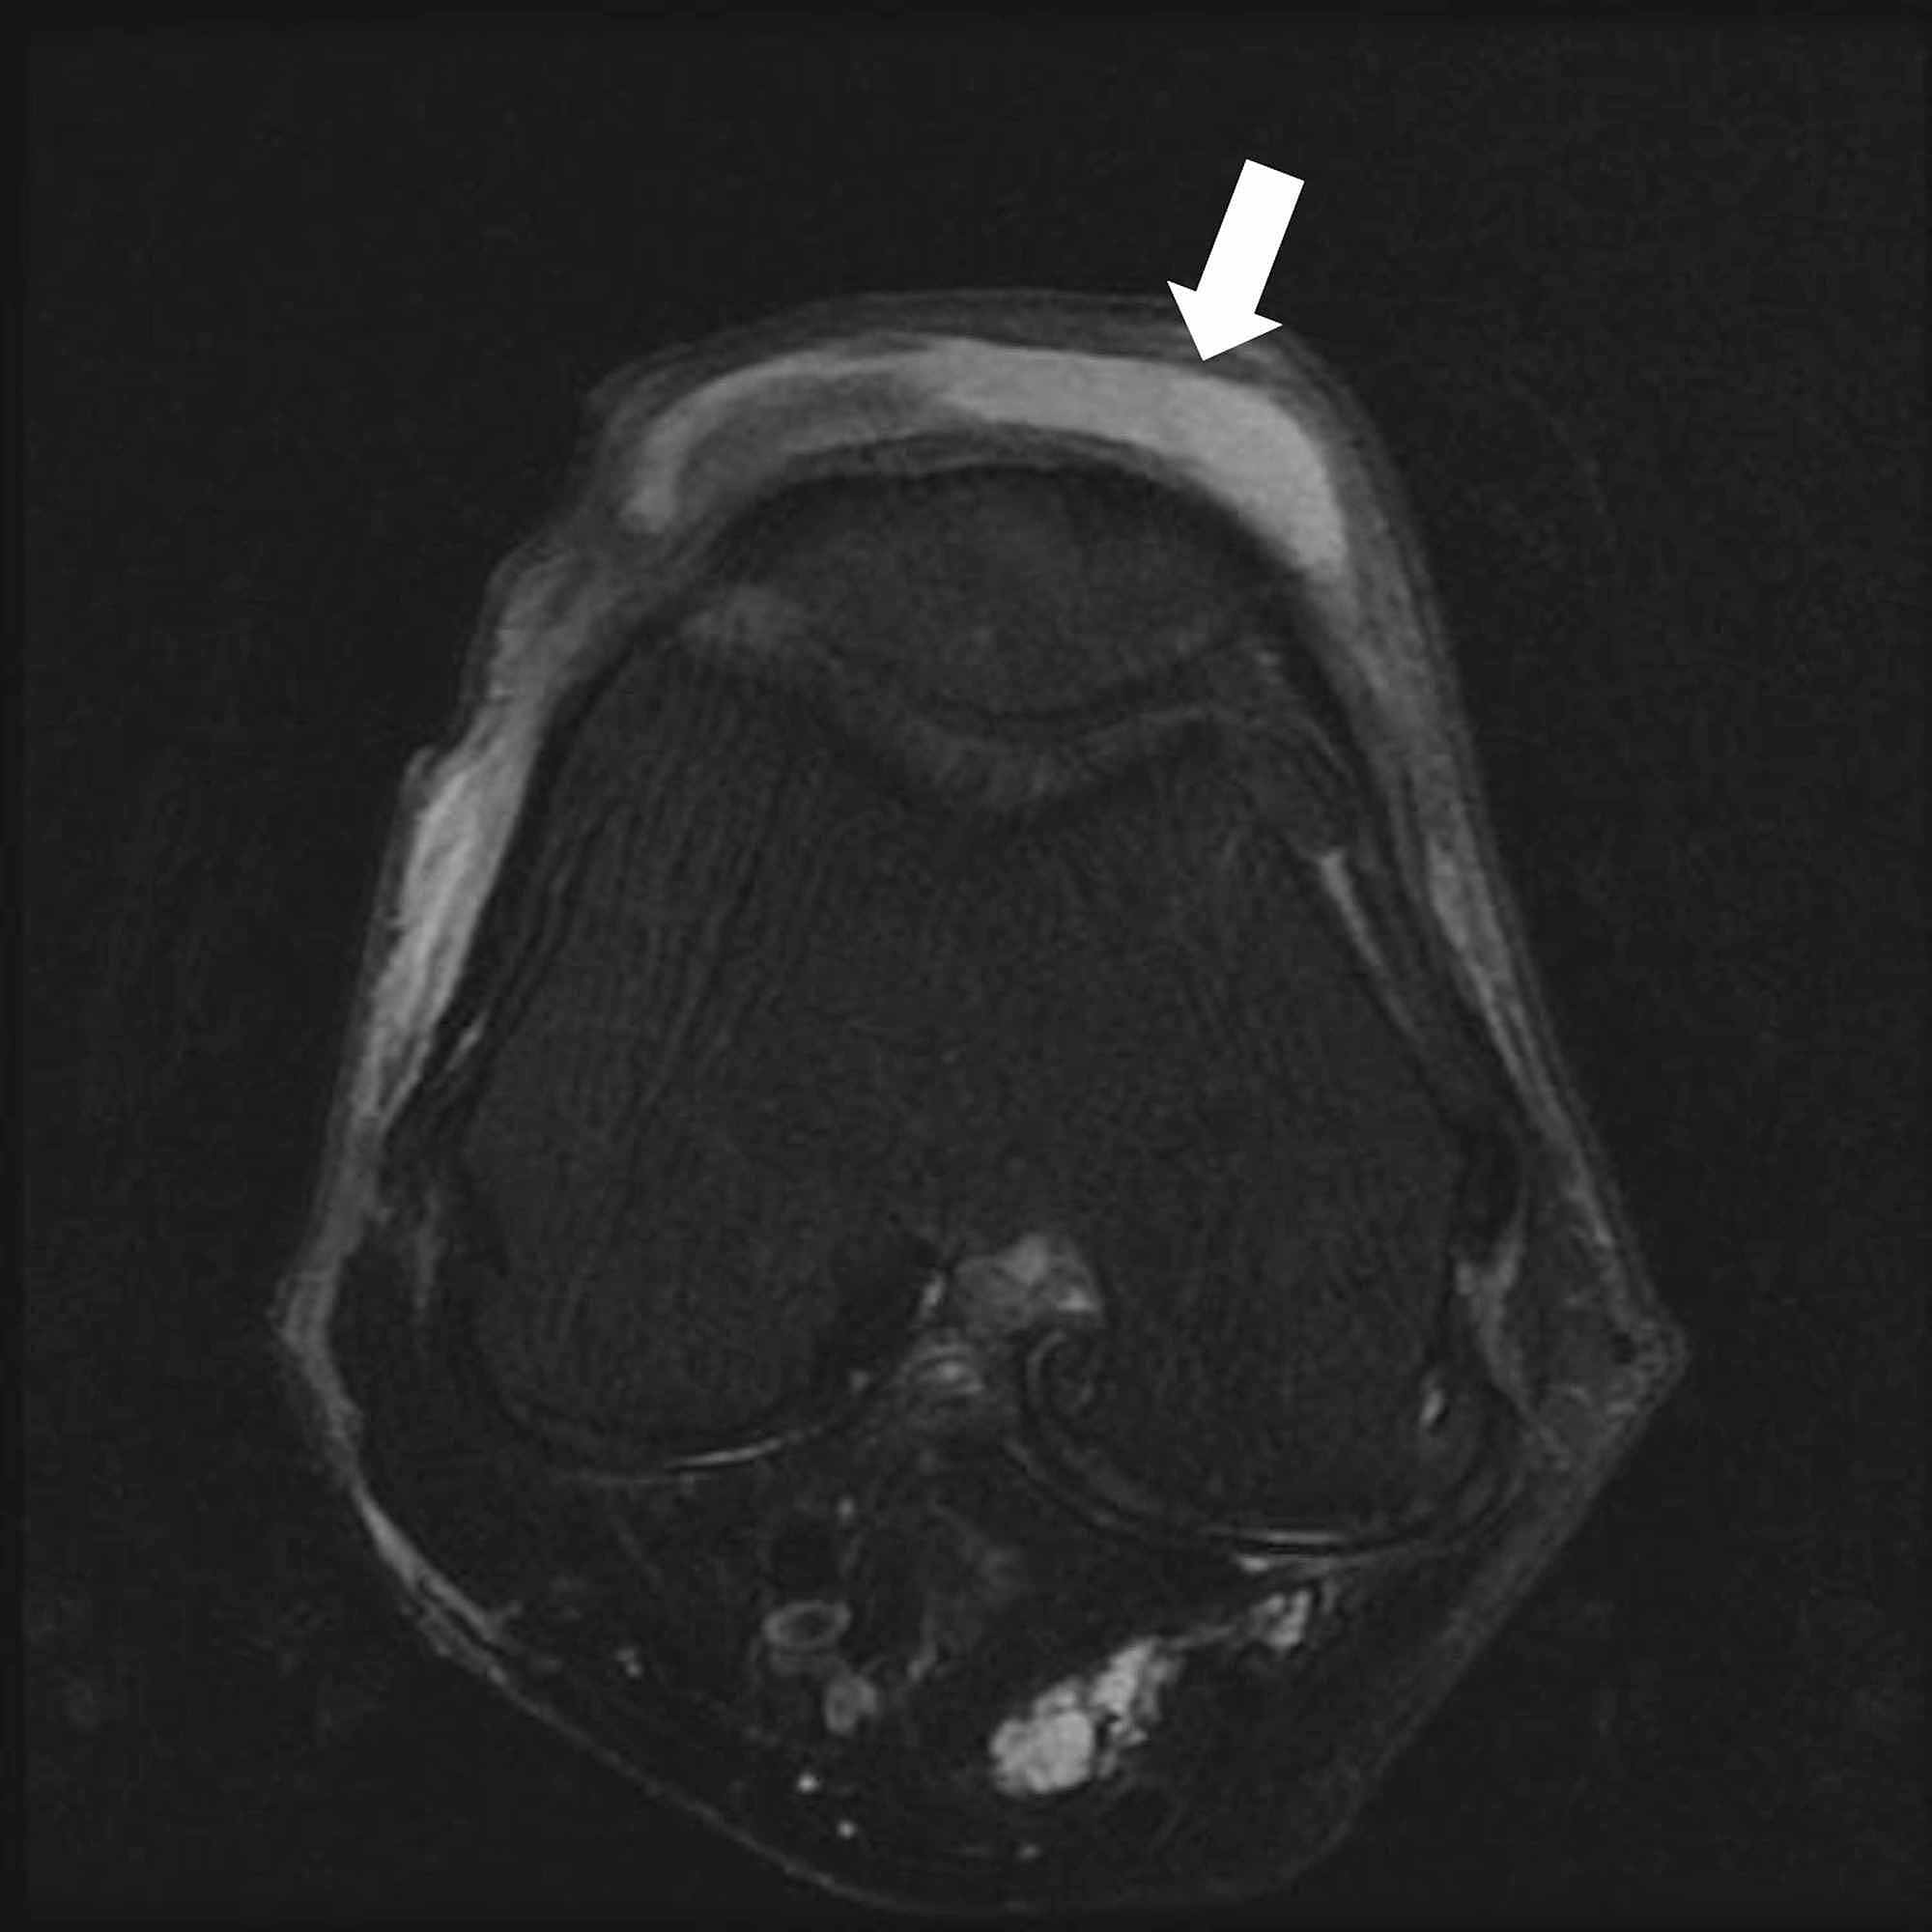

From radsource.us

Knee Bursae Radsource Septic Bursitis In The Knee Web septic bursitis is most likely to occur in bursae that lie just below the skin, such as the prepatellar bursa at the kneecap and. An overview of bursitis and types of aseptic bursitis in. Septic bursitis typically affects bursae located at the knee and elbow. Web septic arthritis can develop when an infection, such as a skin infection or. Septic Bursitis In The Knee.